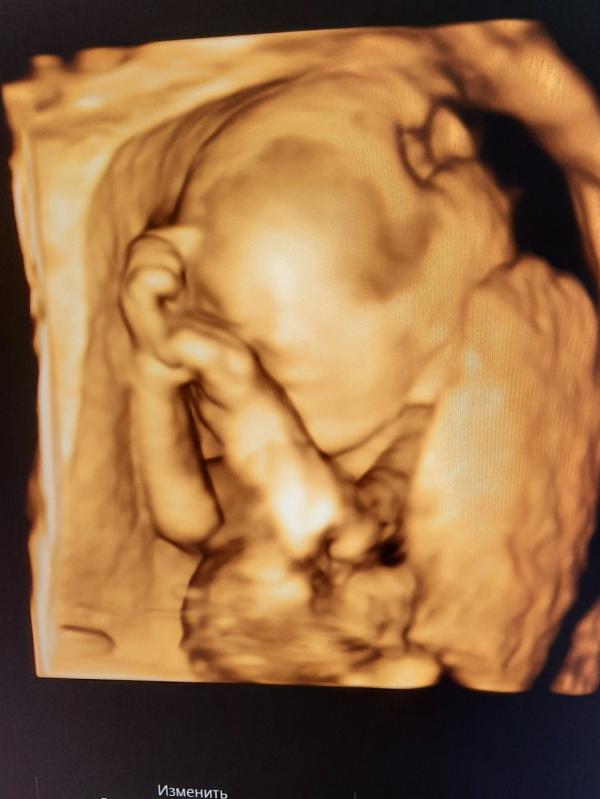

Сегодня была на УЗИ смотрела кровотоки после болезни, ну и конечно увидела своего пузожителя🥰🥰🥰За две недели мы подросли, весим 500 грамм. И наш любимый сынок растёт стеснительным малым💙💙💙Никак не хочет показывать маме своё личико😊😊😊Ждём тебя наш родной💙❤💙❤Пусть останется здесь, в соцсетях я ничего не выкладываю, а поделиться хочется😉😉😉